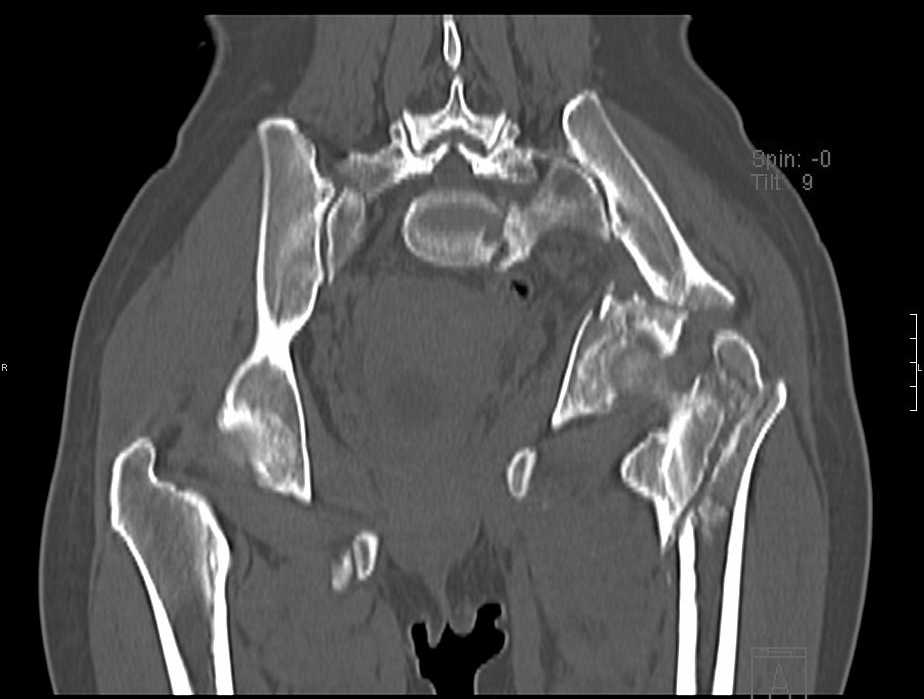

Больная 43 года (промышленный альпинист), 28.07.08 в результате падения с 5 этажа получила политравму: Перелом свода и основания черепа. Вертикально-нестабильное повреждение таза, осложнённое разрывом мочевого пузыря. Чрезвертельный перелом левого бедра. Перелом правой таранной кости, переломовывих правой кубовидной кости. Тупая травма живота, разрыв печени, ушиб почек. Забрюшинная гематома. В день травмы - лапаротомия, ушивание ран печени. Разрыв мочевого пузыря не диагностирован. Течение болезни осложнилось развитием мочевого затёка и обширной пред- и забрюшинной флегмоны, сформировался свищ мочевого пузыря. 19.8.2008 вскрытие, дренировние флегмоны, ревизия мочевого пузыря, обтурация мочевого свища (свищ закрылся в октябре), 1.10.2008 некрэктомия, пластика по Шеде-Лидскому правой кубовидной кости. По результатам КТ диагностирован рак правой почки (диагностическая находка), 8.10.2008 нефрэктомия справа. Переломы велись консервативно. Имеется вертикальное смещение левой половины таза с выраженным отведением крыла (клинически подвижности нет), несросшийся низкий двухколонный перелом левой вертлужной впадины с потерей конгруэнтности, укорочение около5 см, застарелый разрыв лонного сочленения, неправильно сросшиеся переломы обеих ветвей правой лонной кости с укорочением, патологическая подвижность лоно-седалищного фрагмента слева. Правая нижняя конечность неопорна, несмотря на то, что лежа прямую ногу поднимает, ходит на левой ноге (ортопедическая обувь) с костылями, справа тазобедренный ортез. Седалищные нервы работают.Урологи отпустили больную на 6 мес.